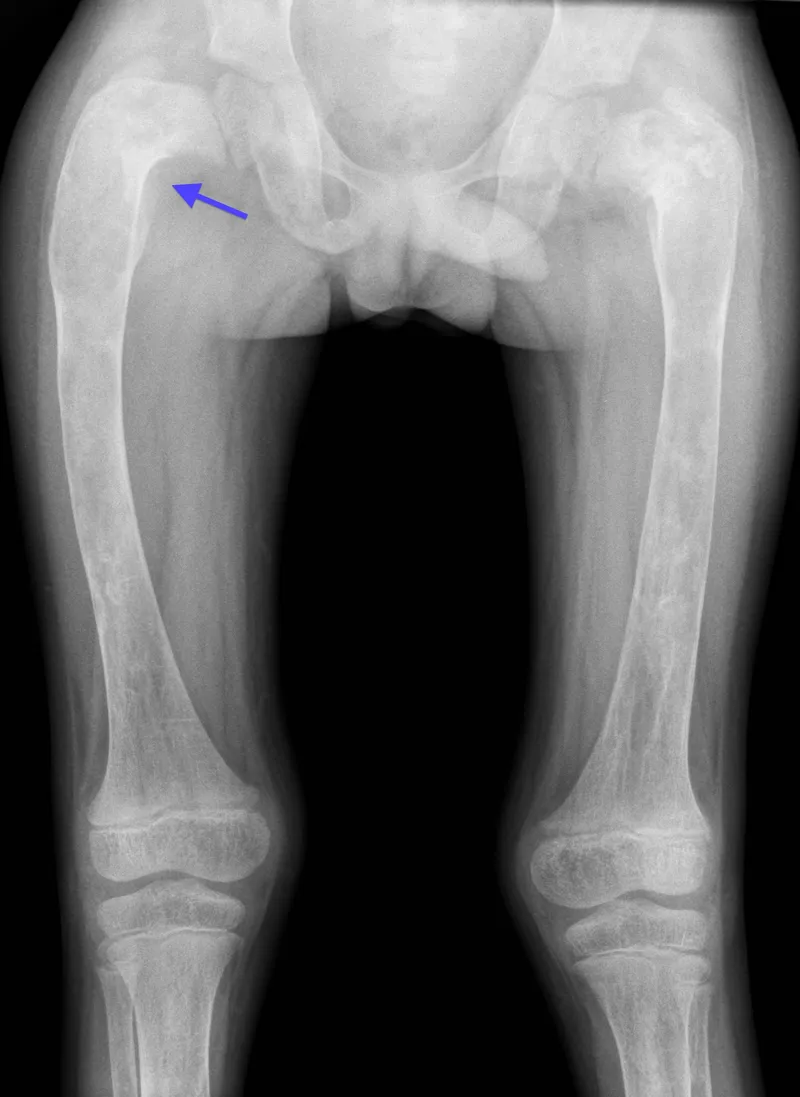

Fibrous Dysplasia (FD)

- GNAS1 mutation; developmental.

- Monostotic or Polyostotic.

- McCune-Albright: Polyostotic, café-au-lait, endocrinopathy. 📌 MAP.

- X-ray: "Ground-glass", Shepherd's crook.

- Histo: "Chinese letters" (woven bone).